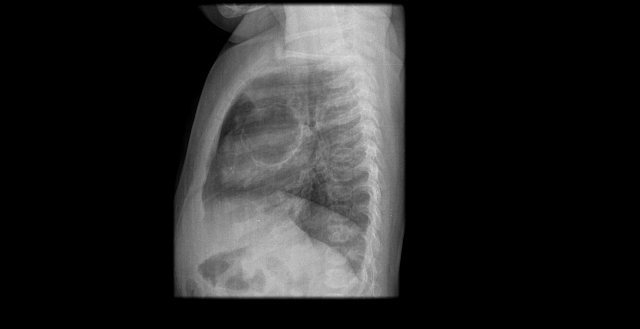

Paciente de 12 años con dolor abdominal. Remitida para estudio de masa intraabdominal.